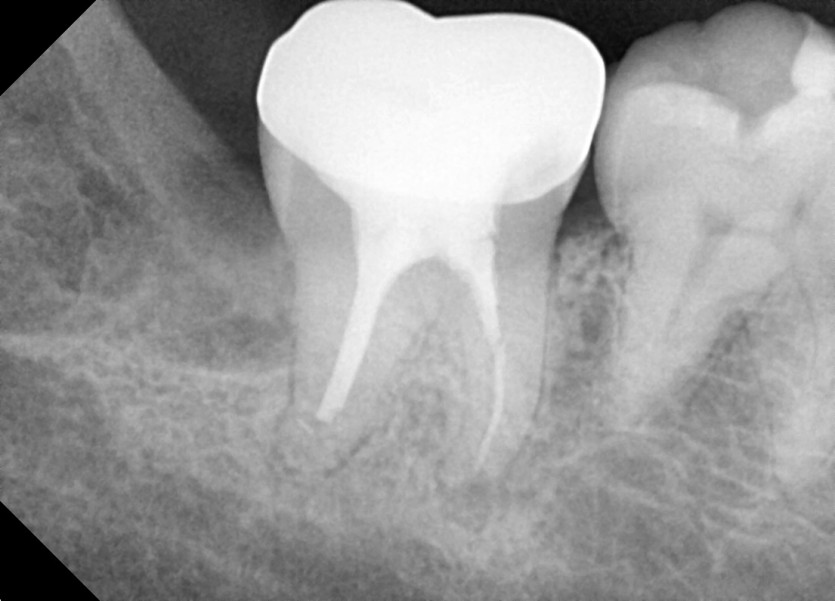

#18,48 사랑니 발치

구강 외과 전문의가 당일 발치했습니다.